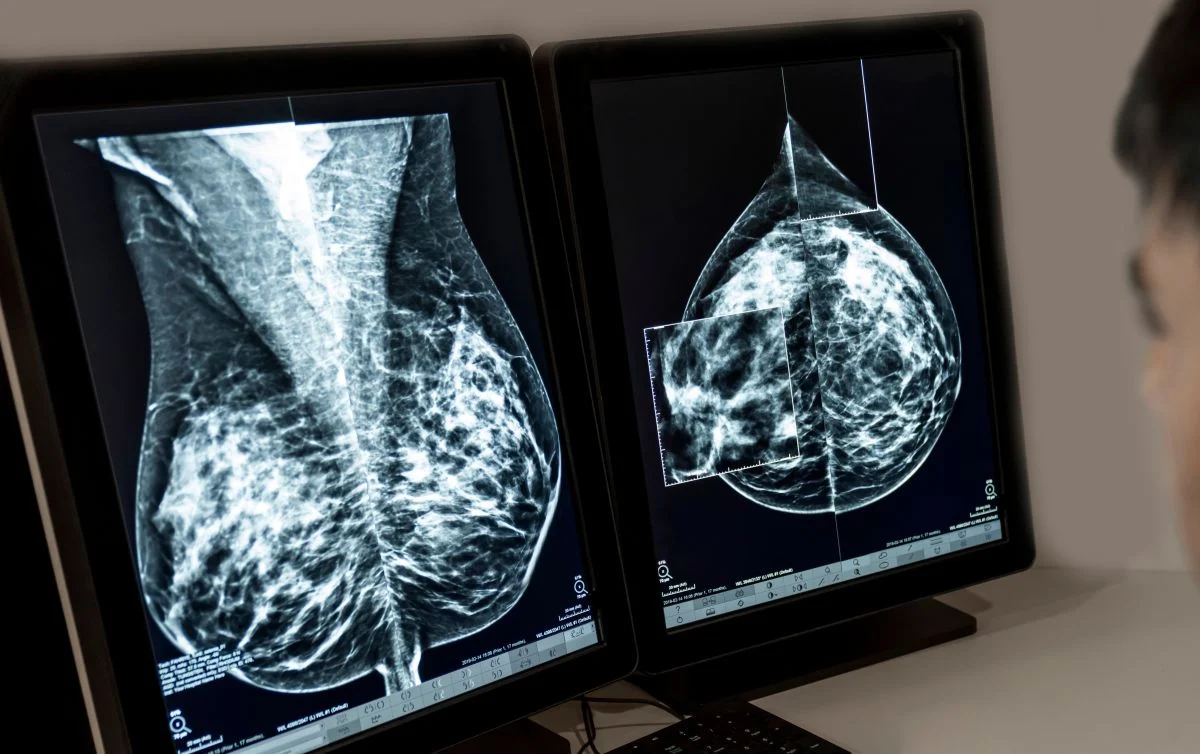

En este contexto, el trasplante pulmonar consiste en una intervención quirúrgica mediante la que se sustituye uno o los dos pulmones enfermos por otros sanos procedentes de un donante humano. El trasplante pulmonar es el único tratamiento aceptado en la fase final de la enfermedad de la silicosis. El objetivo principal del trasplante pulmonar es mejorar la supervivencia de los pacientes.

Según la afección médica del paciente, el trasplante consistirá en reemplazar uno de los pulmones o ambos. En determinadas situaciones, los pulmones pueden trasplantarse junto con el corazón de un donante. Previamente a la operación, se irá haciendo una evaluación, los proveedores de atención médica y el equipo del trasplante revisan tus antecedentes médicos, hacen un examen físico, solicitan varias pruebas, y evalúan tu salud mental y emocional.